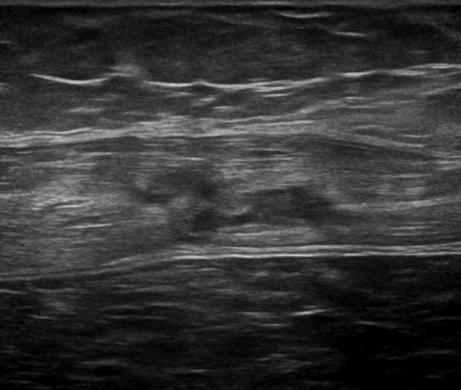

Chấn thương thành bụng - Ảnh 3

Chấn thương thành bụng

» Thông tin: Nam giới – 50 tuổi.

» Lâm sàng: Chấn thương thành bụng.

# Đụng dập, tụ máu cơ thành bụng.